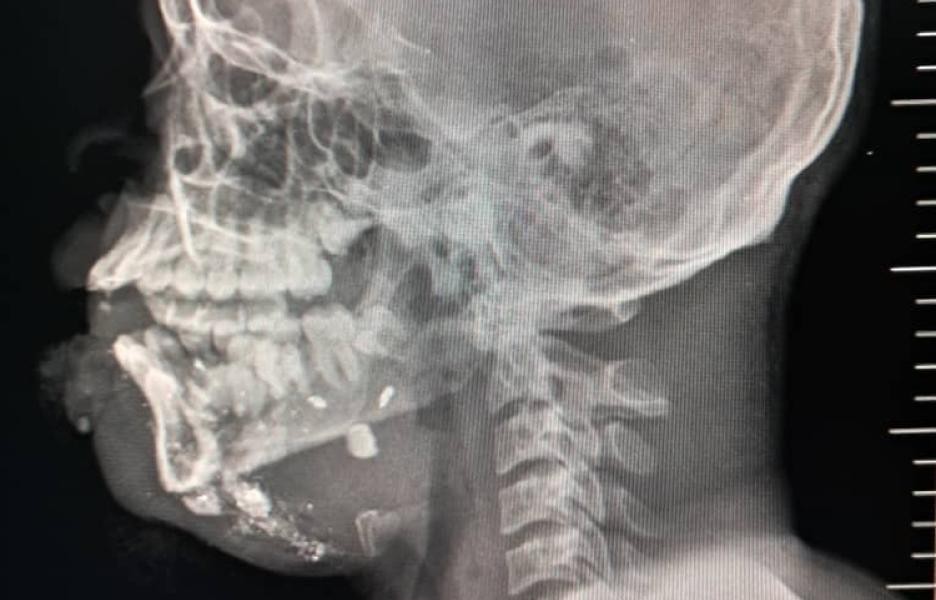

En los primeros seis meses de 2025, MSF atendió a 2.600 supervivientes de violencia sexual, ingresando a 13.300 pacientes en urgencias, incluyendo a 2.267 víctimas de violencia. De estas, el 26% eran menores de edad, un aumento notable respecto al 11% registrado en 2024. La mayoría de estos niños tenían menos de 15 años y un tercio eran niñas. Alarmantemente, uno de cada tres menores ingresados por lesiones relacionadas con la violencia presentaba heridas por bala.

El pasado 20 de septiembre, tras un ataque con drones en Cité Soleil, MSF atendió a 17 heridos. Entre ellos había dos hombres fallecidos a su llegada y varios otros que no sobrevivieron. Este ataque ilustra cómo la población civil se encuentra atrapada entre la amenaza constante de violencia armada y ataques indiscriminados.